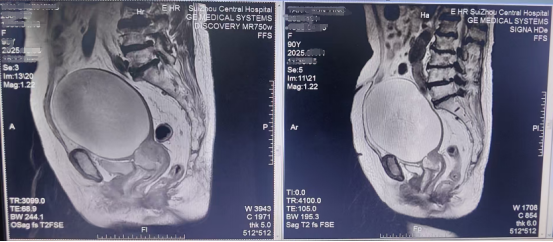

患者2個月前,因宮頸癌導致宮腔大量積液于外院行經腹穿刺引流術后短暫緩解,近日,該患者再次因腹部不適檢查發(fā)現(xiàn)宮腔出現(xiàn)大量積液,形成巨大腹盆腔包塊,這給她帶來了下腹部脹痛不適,同時因嚴重的壓迫周圍臟器,造成排便困難、腎積水、多重耐藥菌感染等,嚴重影響了老人的日常生活和生存質量。老人在家屬的護送下輾轉多家醫(yī)院尋求治療,但因患者高齡、合并基礎疾病多、手術及麻醉風險極高,且積液位置特殊,常規(guī)治療手段效果不佳或風險過大,問題一直未能得到有效解決。

抱著最后的希望,該患者來到隨州市中心醫(yī)院。面對如此高齡、基礎狀況復雜且飽受病痛折磨的患者,腫瘤科聯(lián)合婦科二病區(qū)、無痛中心、超聲影像科、泌尿外科、感染性疾病科、中醫(yī)科等迅速啟動多學科會診(MDT),對患者的病情進行了全面、深入、細致的評估。專家們一致認為:宮腔積液是導致患者全身狀況惡化的首要原因,再次經腹穿刺雖可暫時緩解癥狀,但反復操作導致感染、復發(fā)的難題仍有待解決!最終確定經陰道無痛宮腔鏡檢查+宮腔積液引流+置管術,此術經人體自然腔道操作無新增創(chuàng)傷,宮腔鏡直視下探明宮頸管腔道后放置引流管,可以實現(xiàn)術后持續(xù)引流的目的,更好的解決宮腔積液復發(fā)的困擾。在無痛中心主任尤華、超聲醫(yī)生的協(xié)助下,婦科二病區(qū)主任李進實施微創(chuàng)的宮腔鏡檢查+宮腔積液引流術+宮腔引流管放置術,患者的“隆起腹”消失了,患者術后恢復良好。